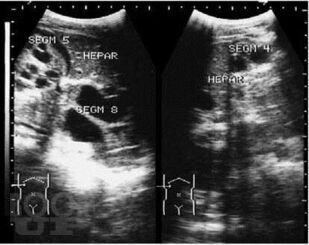

В Практическом руководстве отражены вопросы клинико-лабораторно-лучевой диагностики эхинококкоза печени с сипользованием УЗИ, РКТ, МРТ и современные аспекты лечения. Практическое руководство предназначено для специалистов лучевой, клинической, лабораторной диагностики, терапевтов, гепатологов, хирургов, онкологов.